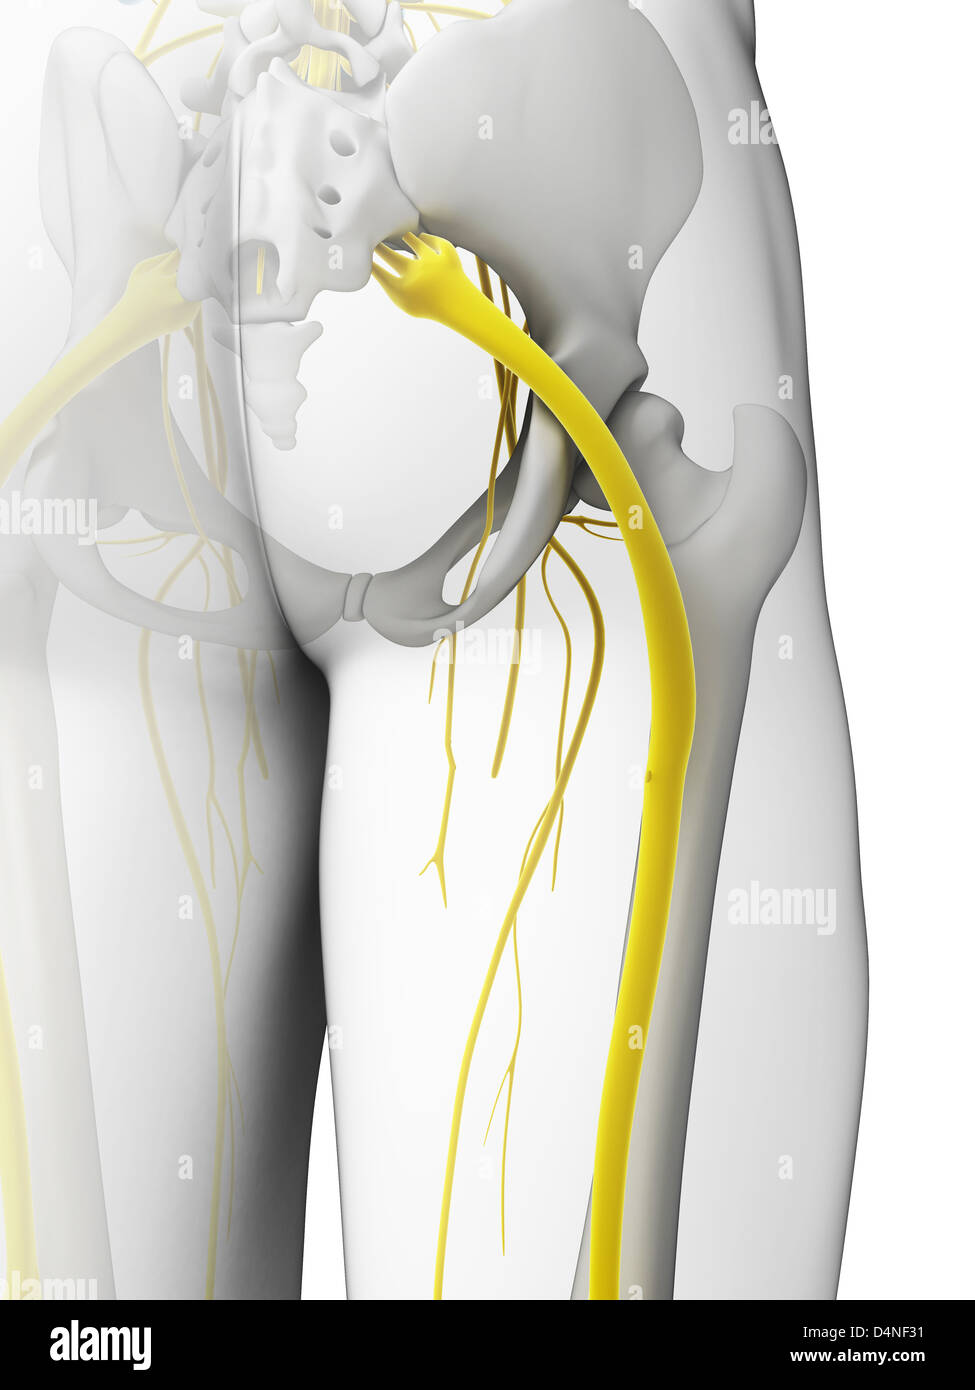

Nerf sciatique Banque D'Imageshttps://www.alamyimages.fr/image-license-details/?v=1https://www.alamyimages.fr/photo-image-nerf-sciatique-54609549.html

Nerf sciatique Banque D'Imageshttps://www.alamyimages.fr/image-license-details/?v=1https://www.alamyimages.fr/photo-image-nerf-sciatique-54609549.htmlRFD4RK11–Nerf sciatique

Nerf sciatique Banque D'Imageshttps://www.alamyimages.fr/image-license-details/?v=1https://www.alamyimages.fr/photo-image-nerf-sciatique-54562576.html

Nerf sciatique Banque D'Imageshttps://www.alamyimages.fr/image-license-details/?v=1https://www.alamyimages.fr/photo-image-nerf-sciatique-54562576.htmlRFD4NF3C–Nerf sciatique

Nerf sciatique Banque D'Imageshttps://www.alamyimages.fr/image-license-details/?v=1https://www.alamyimages.fr/photo-image-nerf-sciatique-54562565.html

Nerf sciatique Banque D'Imageshttps://www.alamyimages.fr/image-license-details/?v=1https://www.alamyimages.fr/photo-image-nerf-sciatique-54562565.htmlRFD4NF31–Nerf sciatique